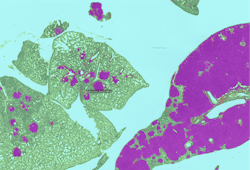

Evaluating potential toxicity that may result in decreased fertility is an important component of the development testing funnel. In one assay required by regulators, the toxicologic pathologist assesses a test agent’s effect on the ovary by enumerating the number of primordial and primary follicles. This painstaking work is both time consuming and prone to intra- and inter-observer variability. To improve the counting process, additional procedures have been instituted including immunohistochemistry and standard image analysis to facilitate the counting.6 AI-CNNs have now been developed by toxicologic pathologists and others to classify and count these structures in standard hematoxylin and eosin-stained slides in an automated fashion.7,8 (Figure 1)

Figure 1: Workflow for training and testing of AI-CNN (Aiforia Create) for ovarian follicle counting; Figure 1B: AI-CNN identifying and counting primary follicle (left) but not counting a potential primary follicle (right) that did not meet requirements (nucleus not clearly present)

By simply digitizing the microscopic slide, the AI-CNN algorithm in seconds can complete what takes several minutes by a trained observer. The algorithm can be cross-trained to evaluate the ovary from different toxicology models quickly or adapted to answer specific investigative questions that the laboratory may have concerning the time course or mechanism of toxicity. The AI-CNN algorithm can be placed in the “cloud” and the same algorithm be used by multiple pathologists globally.9 This simplifies the need for software installations and ensures that laboratories may be consistent. Similar approaches have been developed for the testes as well and for quantifying mitoses in various tissues. AI-CNNs promise to automate these types of redundant tasks for the toxicologic pathologist.